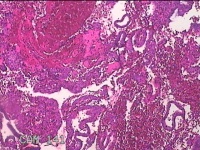

宫内刮出物

性别

女

年龄

41岁

临床诊断

异常子宫出血;女性盆腔炎

一般病史

阴道出血淋漓不净1月。

标本名称

大体所见

灰白暗红色不规则碎组织4x3.8x0.8cm一堆。